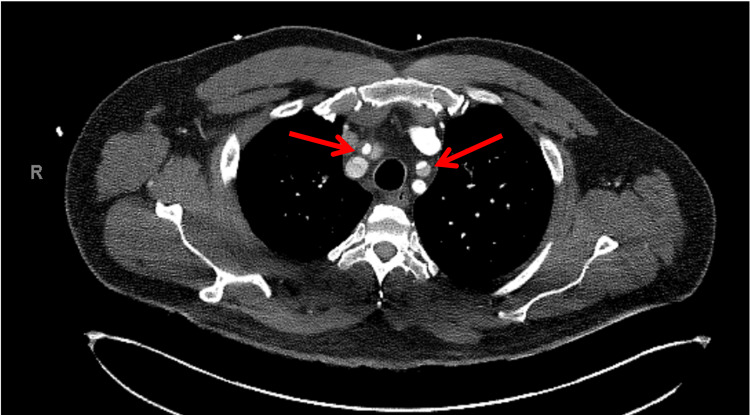

In view of chest pain associated with positive cardiac biomarkers, he was admitted to the Coronary Care Unit on intravenous nitroglycerin. While waiting for his admission, he suddenly had recurrent chest pain associated with marked hypotension (75/43 mmHg), for which the intravenous nitroglycerin was discontinued, fluid resuscitation was provided, and he was temporarily started on intravenous norepinephrine. The on-call cardiology team was contacted for an emergent evaluation. Subsequent ECG showed nonspecific ST-segment changes in leads V5-V6 (Figure 1). An emergent bedside echocardiogram revealed a moderate pericardial effusion of hemodynamic significance (Figure 2), as suggested by partial right ventricular chamber collapse (Figure 3) early in diastole and a plethoric non-collapsing inferior vena cava. The pericardial effusion also contained echogenic strands, which are highly concerning for blood clots. Additionally, a moderate to severe aortic valve insufficiency (Figure 4) was present according to color Doppler findings and pressure half-time assessment (315 ms). An intimal flap was visualized on the ascending and descending aorta, suggesting an extensive AD (Figures 2–6). A computer tomographic angiogram (CTA) of the chest and abdomen revealed a large pericardial effusion with an extensive AD extending from the level of the ascending aorta into his right brachiocephalic artery, the right and left common carotid arteries, and inferiorly to the right iliac artery (Figures 7–10), although not occlusive in diameter (or clinically). These findings were consistent with an extensive Stanford type-A AD with rupture into the pericardium, for which volume expansion and vasopressors were provided and emergently operated on the same day. The surgery included an open pericardiotomy with pericardial blood drainage, replacement of the ascending aorta from just above the commissure to the take-off of the innominate artery, partial replacement of the aortic arch, and aortic valve repair with successful results. Multiple intraoperative packed red blood cell units (8), fresh frozen plasma units (4), cryoprecipitate units (10), and platelet apheresis (3) were provided in view of bleeding complications related to the arrival provision of dual antiplatelet and anticoagulation therapy prior to the diagnosis of AD.